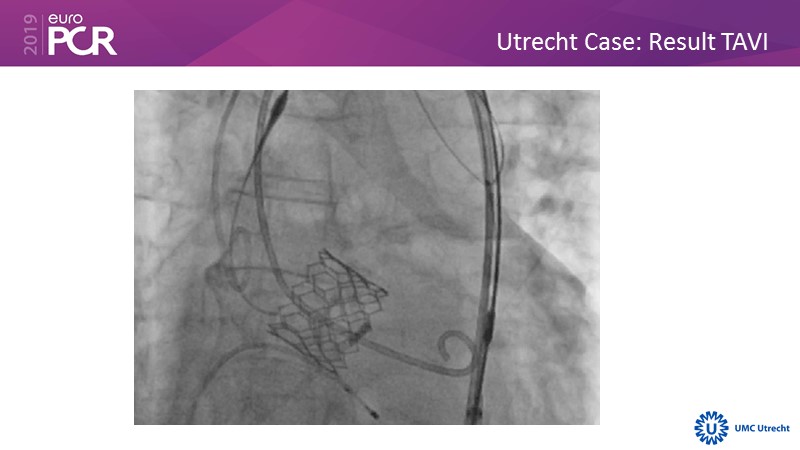

Consult this session to hear the latest update on the US REFLECT phase II trial, to learn about the EU experience with the TriGUARD 3 CEP device and to learn about Keystone Heart's EU roadmap.

- To learn about the EU experience with the TriGUARD 3 CEP device